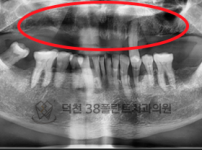

치료전후